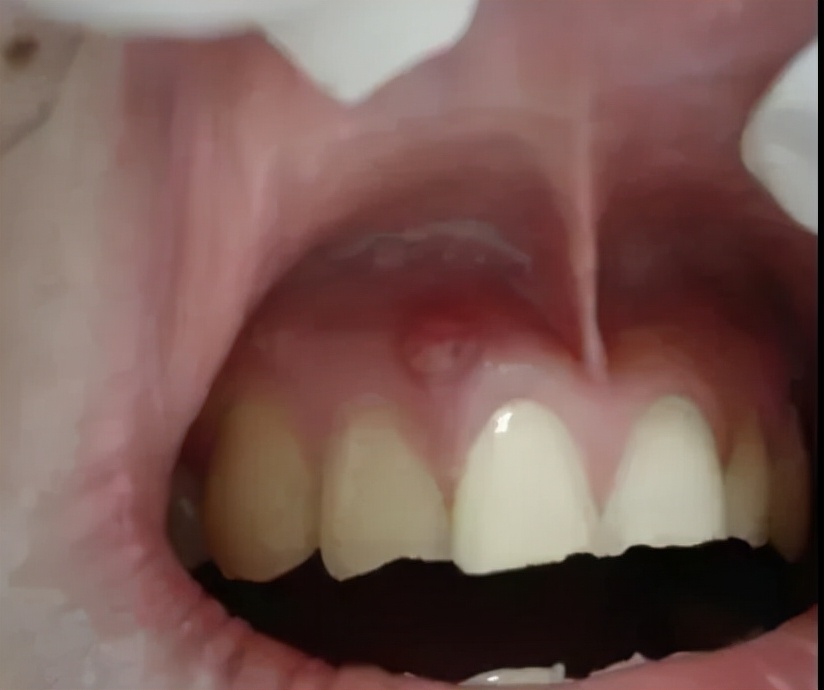

看表面是一个脓包,实则牙龈内的牙根已经发炎,细菌感染牙髓演变成牙根炎症,牙槽骨遭到炎症的影响,所以牙龈上才会鼓起一个脓包。从根尖到牙根的瘘管,脓包内产生的分泌物由此流出。如果你出现这样的问题,必须要及时去看医生才行,否则情况会加重!

脓包需要怎么处理主要看是由什么引起的!一般有牙根发炎和牙周炎引起的!

①根尖炎症导致的,则需要拍牙片检查下根尖周组织破坏情况,再来评估患牙是否有保留价值。很简单,无法保留则拔掉;能够保留就要根管治疗,并且在牙龈下做切口排脓,放药,待几天好转了之后,就可以补牙修复了。